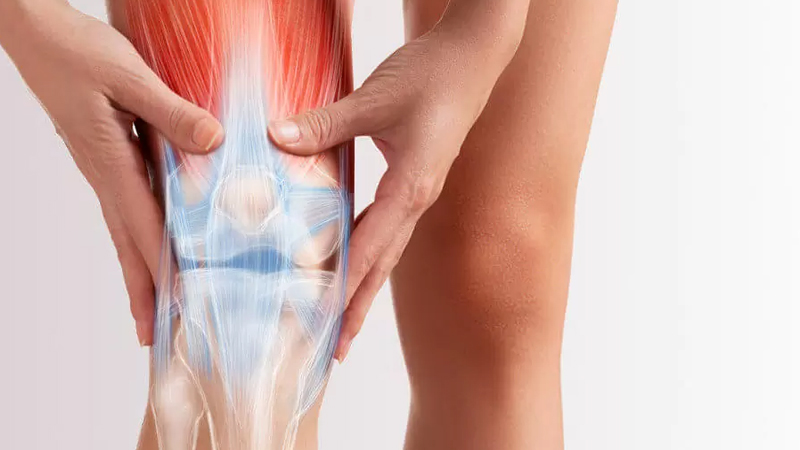

Knee arthroplasty surgery

Replacement of knee joint and patella

The main goal of knee joint replacement surgery is to improve the quality of life of a person who has suffered severe damage and impairment in the knee joint. This surgery can help a person reduce pain, improve knee movement and function, and make daily activities easier.

Specialist in sports injuries

Knee sports injuries can include things like anterior or posterior cruciate ligament injury, meniscus injury, knee end zone injury, patella injury (xenopathy) and tendon injury around the knee. These injuries may result from sports activities such as football, basketball, running or repetitive sports.

- Ligament injuries around the knee

- Articular cartilage and meniscus damage

- Dislocation of the knee joint or knee joint